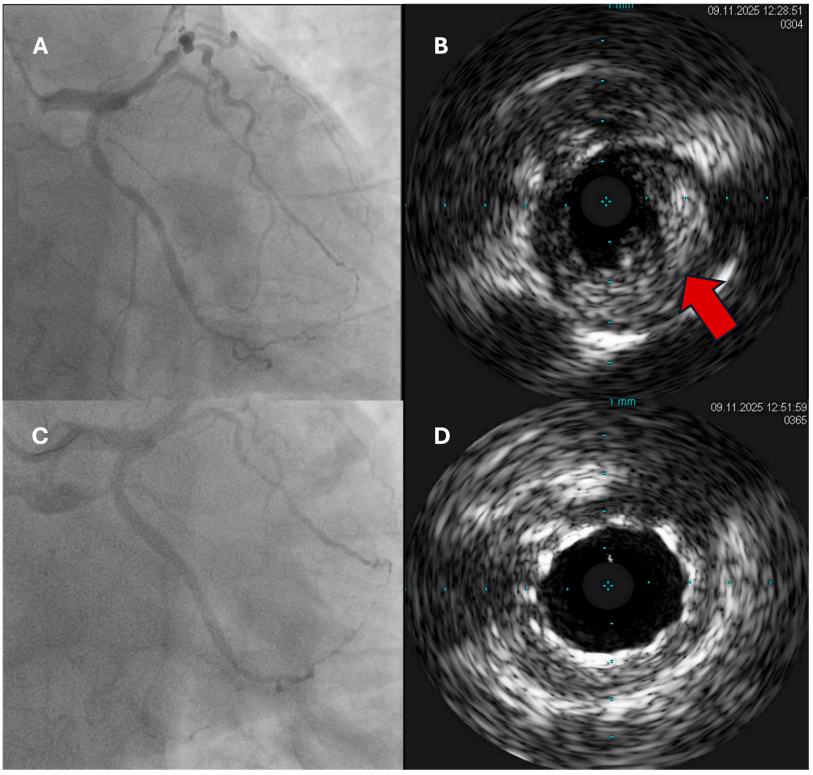

血管内影像(IVUS/OCT)已成为优化ACS患者PCI的核心工具,能改善支架尺寸选择、扩张与贴壁,从而减少不良事件(图1)。一项大型当代荟萃分析证实,与单纯造影引导相比,影像引导的支架置入能显著降低复合不良结局(图2)。在功能学评估方面,FLOWER-MI试验显示,在STEMI患者中,FFR引导的完全血运重建并未优于造影引导。当前实践趋势倾向于:对ACS PCI(尤其是左主干、分叉、钙化等复杂病变)常规使用影像引导;在患者病情稳定后,可选择性使用功能学来辅助非罪犯病变的决策。

图1. IVUS在ACS患者PPCI中应用示例。 (A) 诊断性冠状动脉造影显示LAD罪犯病变;(B) IVUS显示罪犯病变伴大的软斑块(箭头)压迫管腔;(C) LAD病变成功置入药物洗脱支架;(D) IVUS显示管腔完全开放及支架成功置入。